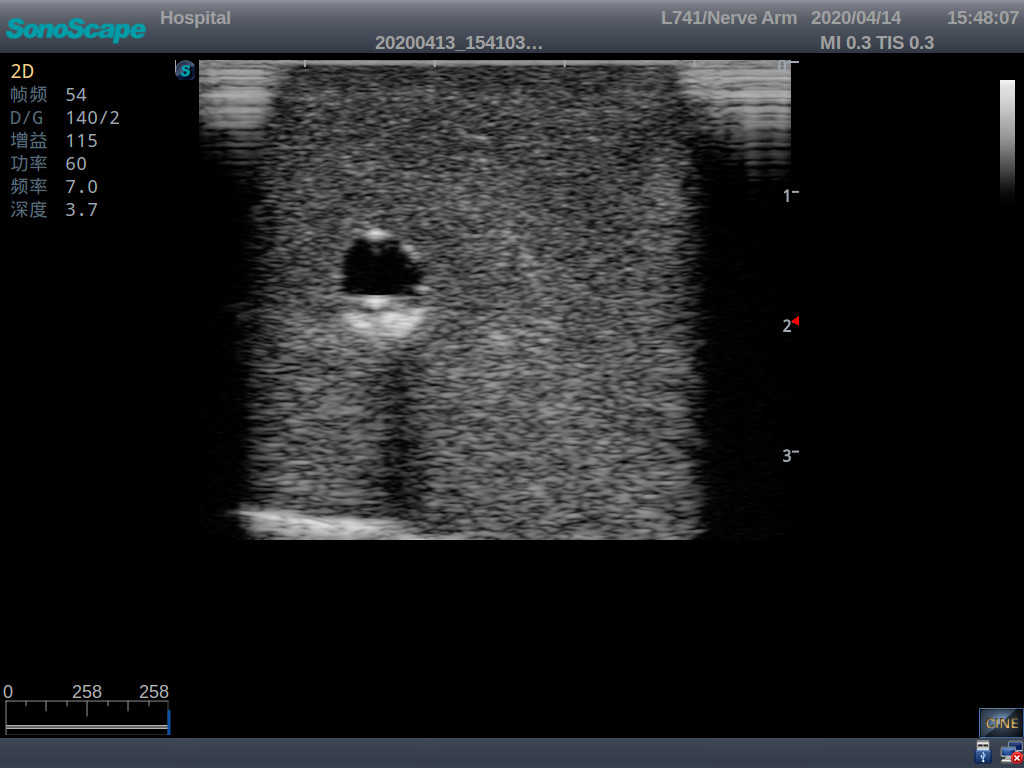

Model TYE1510.1

1)   Made of high molecular polymer ultrasound material, close to the real skin

2)   It can be used by real ultrasound machines

3)   Clear and real images of the tissues and organs (basilic vein and superior vena cava)

5)   Observe the guide wire marches

6)   Detect whether the catheter is properly placed